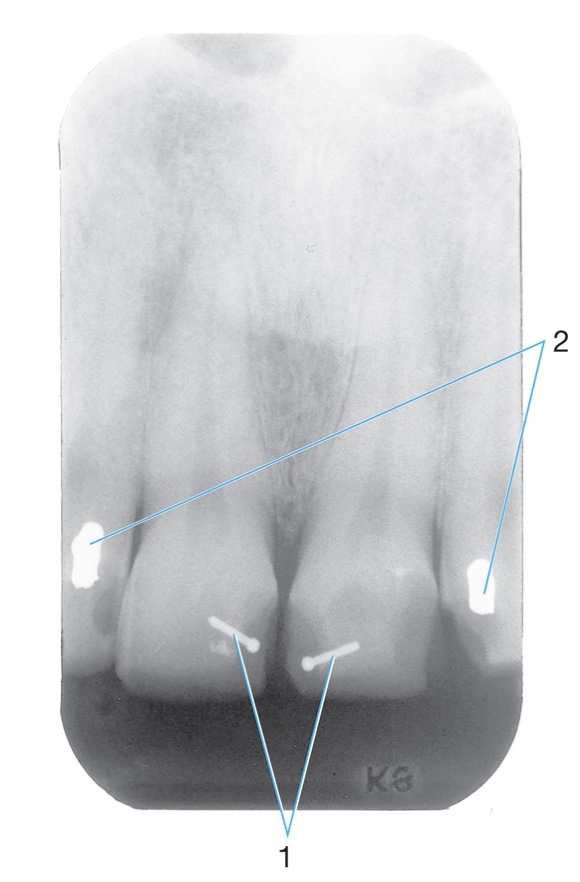

1.

Dental base

Opening or hole in bone located at the midline of the anterior portion of the

hard palate directly posterior to the maxillary central incisors.

Radiolucent/Radiopaque?

Incisive foramen #1

Radiolucent

2.

Radiopaque amalgam restorations